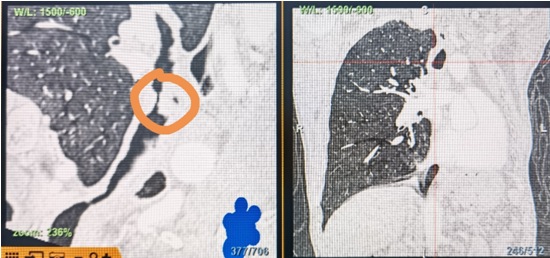

時(shí)間就是生命!了解患者病情后,歐陽(yáng)海峰立刻啟動(dòng)氣道梗阻緊急救治通道,協(xié)調(diào)院前轉(zhuǎn)運(yùn),急診快速入院流程。凌晨患者入院胸部CT顯示,現(xiàn)存唯一的呼吸通道在右主支氣管處,狹窄處僅約3毫米,患者命懸一線!

運(yùn)用呼吸介入技術(shù),軟硬鏡結(jié)合快速開通氣道,是患者目前唯一可行的治療方案,手術(shù)刻不容緩!但存在麻醉后氣道完全塌陷閉合、大出血、窒息等巨大風(fēng)險(xiǎn)。患者此前接連轉(zhuǎn)診3家醫(yī)院,均建議保守支持治療或轉(zhuǎn)院。歐陽(yáng)海峰詳細(xì)了解患者病史,全面評(píng)估影像檢查結(jié)果后,決定盡快進(jìn)行手術(shù),組織醫(yī)護(hù)團(tuán)隊(duì)對(duì)患者進(jìn)行持續(xù)密切監(jiān)測(cè),充分保障其術(shù)前安全。